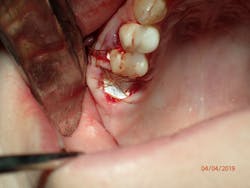

As direct implant costs have gone down, the simplification and efficiency of many implant procedures have contributed to what many are calling the “golden age of implant dentistry.” The advent of short implants—and research articles backing the success rate of short implants—has reduced the need for more extensive grafting procedures. This is one clinical area that has allowed more general practitioners to place more implants due to the simplified sinus-area procedures. In areas of 6 mm or more of maxillary bone height, clinicians are able to provide a minimally invasive sinus bump and achieve bicortical stabilization. Implants such as the iHex and MorsTorq were designed with a rounded end to safely provide this procedure. The taper of these and similar systems also protects the implant from being lodged apically into the sinus cavity, thus making it user-friendly for beginner to intermediate implantologists.

Therefore, if a patient has 5 mm of available bone height from the sinus floor, a maximum of 5 mm is prudent to expect from an indirect lift; therefore, an 8 mm to 10 mm implant is the ideal choice. The tapered iHex or MorsTorq implant provides safety when dealing with sinus areas, for three reasons. First, the taper helps prevent overinsertion toward the sinus cavity. Second, the abutment and transfer attached to the implant allows for more control. Finally, the rounded apex helps reflect the sinus floor without creating damage (figures 1-6).